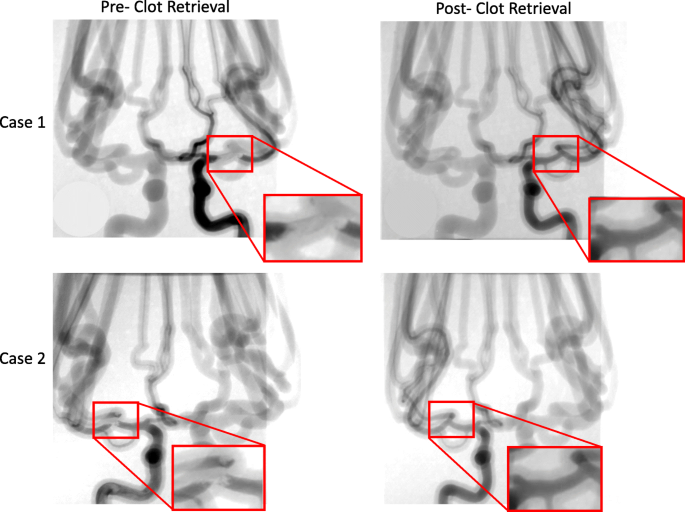

Using these phantoms, angiograms were captured before recanalization, showing the extent of the thrombus, and after the thrombectomy to determine the recanalization outcome. Figure 5 displays the change in blood flow before and after the stent retriever has been deployed. Figure 6 depicts a montage of the contrast flowing through a 3D printed model after both an unsuccessful and a successful mechanical thrombectomy simulated procedure.

Angiograms were taken both pre- and post- stent retriever thrombectomy was completed. Pre- clot retrieval, there is very little or no contrast flowing at the location of the clot. Post- clot retrieval there is contrast flowing through the part of the vessel where the clot was removed. Case 1 and case 2 in this figure display this significant change in fluidic flow at the location of the clot. The red boxes are enlarged views of the specific locations where the contrast flow changes